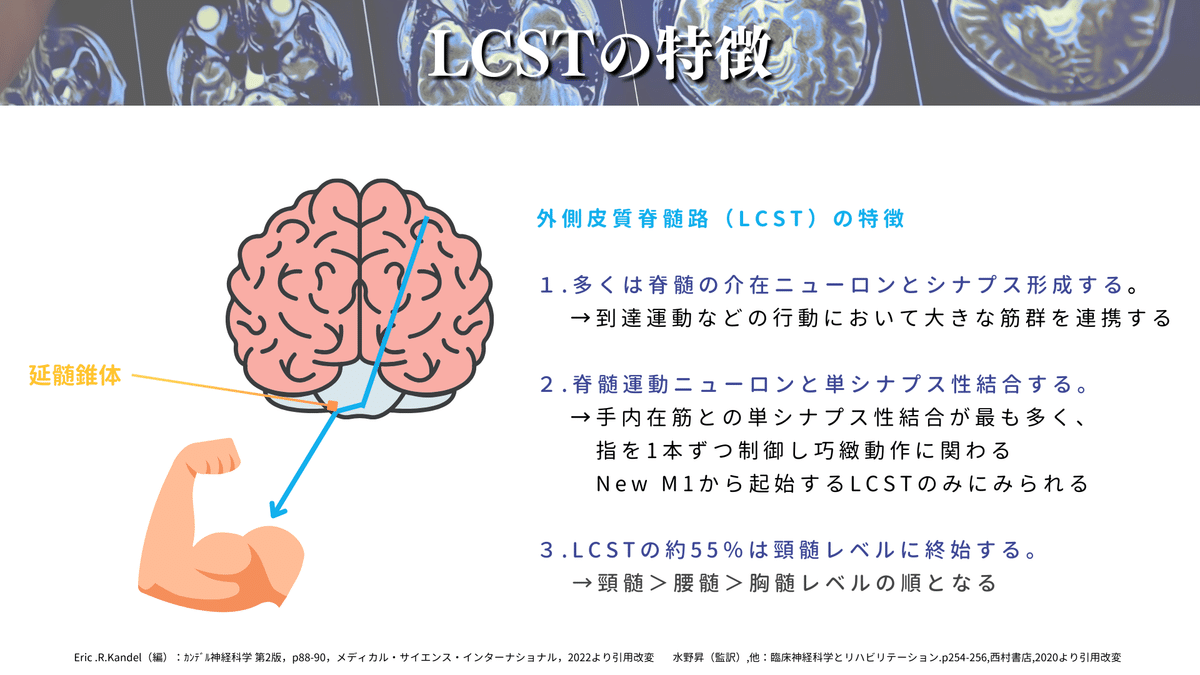

CSTは外側皮質脊髄路(LCST)と前皮質脊髄路(ACST)に分かれますが、80〜90%がLCSTですので、CST=LCSTという認識でもOKです👌

LCSTは特に上肢・手指との関連性が強く、LCSTの55%は頸髄レベルに終止すると言われています🖐️

橋のレベルは他の脳幹とは少し性質が異なり、右図のようにCSTが分散します!

橋底部は主に橋核から構成されていて、その橋核ニューロンから小脳に向かう横走線維(横橋線維と同義)が大部分を占めています😳

つまり、橋底部は横に走る線維が多く、下降するCSTはその線維を避けて通過しないといけないので、一度CSTは分散する必要があります!(心太みたいなイメージです🎐)

なので、橋ではCSTの密度が薄くなるので、脳梗塞などで損傷をされてもCSTの損傷度合いが小さく済むケースが多く、運動麻痺が軽症になる場合があります✨

CSTは延髄錐体で80〜90%が交叉して脊髄の側索を通ります。これをLCSTと言います🖐️

残りの線維は非交叉性で前皮質脊髄路(ACST)と言いまして、脊髄の前索を下降していきます🏃♀️

ACSTの主な特徴は以下になります⬇️

・胸髄レベルでほぼ消失

・脊髄レベルでは一部が前白交連で交叉する

・普段はマスキングされていることが多い

・ヒトでは個体差に富み、体幹の制御に関わることもある